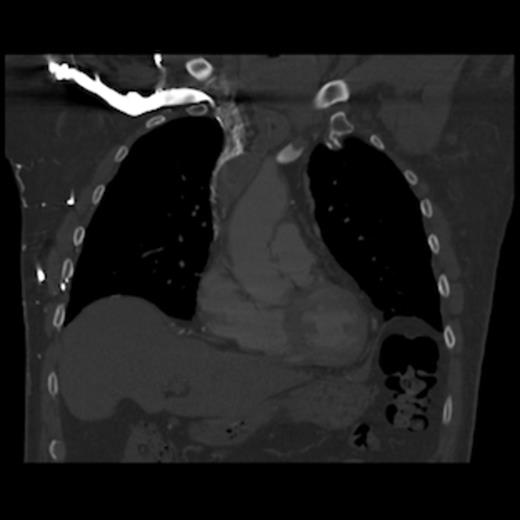

A 67-year old gentleman presented with progressive head and neck swelling and discomfort for several months. His symptoms were pronounced by bending over or straining in the bathroom. His symptoms worsened and he was referred for thoracic surgery consultation after a mass was seen on chest x-ray. He was diagnosed with SVC syndrome secondary to a mediastinal mass, demonstrated best by computed tomography (CT) [Figures 1, 2, 3].

CT of the chest (coronal section) with intravenous contrast: demonstrates complete obstruction of the superior vena cava by a large intramural thrombus that extends into brachiocephalic vein